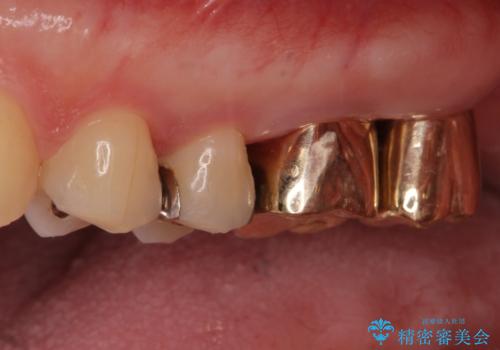

- 銀歯をやりかえたいが他院で抜歯と言われセカンドオピニオンで来院。適合の悪い被せ物が入っており、まずは古い材料、虫歯をとり保存可能か確かめる必要があり、拡大鏡下で全て取り除いたら歯質が歯茎の中まで虫歯がありました。このまま無理やり型取りをして被せ物を作っても不適合な被せ物が入る可能性が高いため歯茎を切り取る手術(ディスタルウェッジ)を行いました。そして再根管治療を行いゴールドの被せ物で治療を行いました。

適合の良い被せ物が入り大変満足して頂けました。